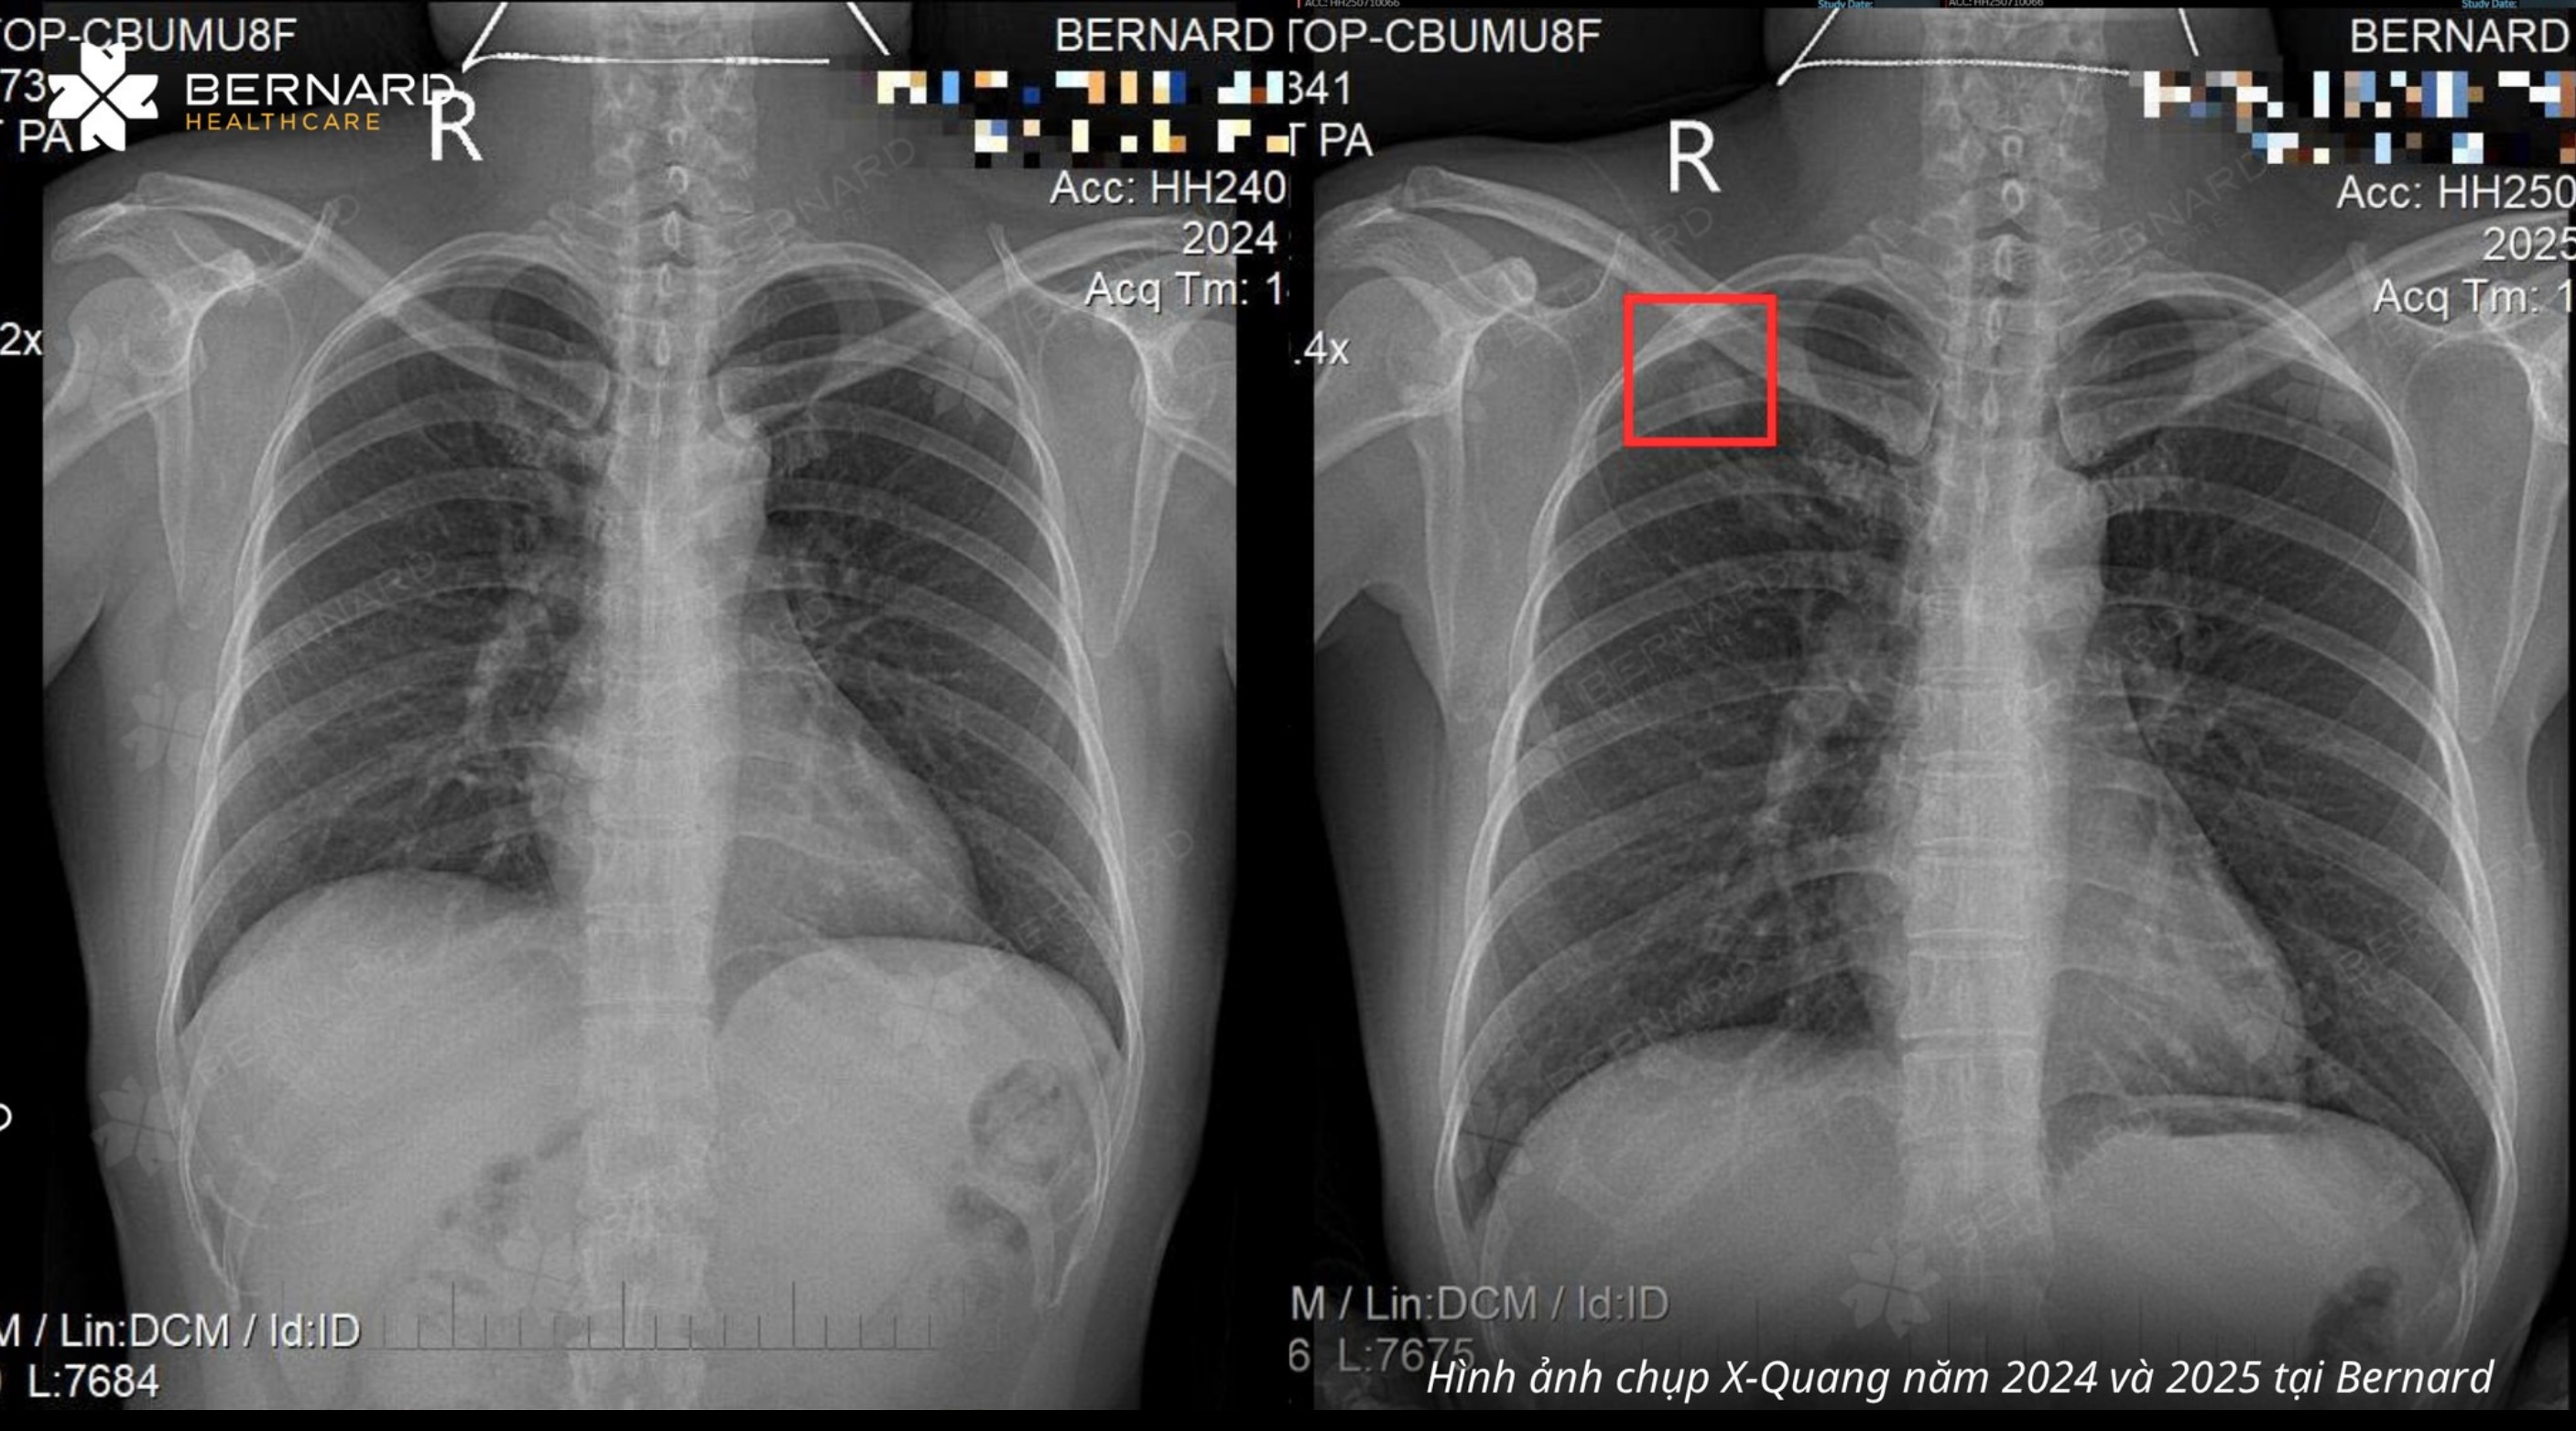

Tuy nhiên, khi đối chiếu phim X-quang ngực năm 2025 với phim năm 2024, bác sĩ phát hiện một nốt mờ vùng hạ đòn phổi phải, hình ảnh không xuất hiện ở lần khám năm trước. Đây là dấu hiệu gợi ý tổn thương mới xuất hiện và cần đánh giá thêm.